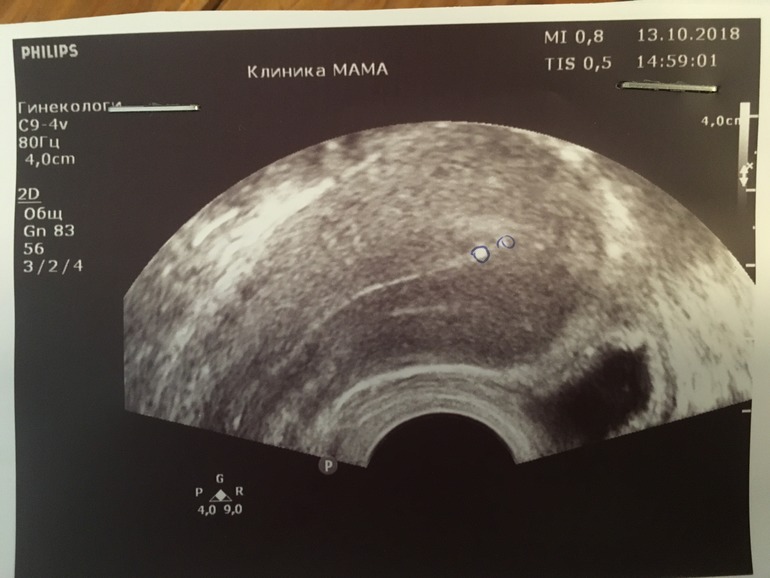

ГистероскопияДевочки, после зб прохожу обследования. На узи в матке врач увидел какие то включения.

тк день цикла был первый подождали конца месячных и на 10й дц сделали узи повторно, тоже самое.

для опытных профессоров сообщества зачатие я приложу фото))))